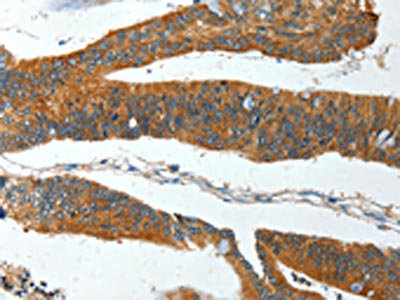

The image on the left is immunohistochemistry of paraffin-embedded Human thyroid cancer tissue using CSB-PA634409(IL12RB1 Antibody) at dilution 1/15, on the right is treated with fusion protein. (Original magnification: ×200)

The image on the left is immunohistochemistry of paraffin-embedded Human colon cancer tissue using CSB-PA634409(IL12RB1 Antibody) at dilution 1/15, on the right is treated with fusion protein. (Original magnification: ×200)